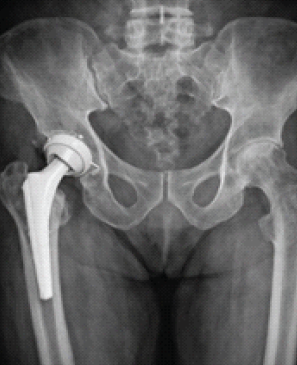

Complex Reconstruction of Post-traumatic Fracture Dislocation Hip: The Anchor Total Hip Arthroplasty Following Failed Index Surgery

Vijay G Goni , Deepak Kumar , P K Vivek , Manjunath Nishani , M Harshith , V S Sumukha ………………………………p.182-187